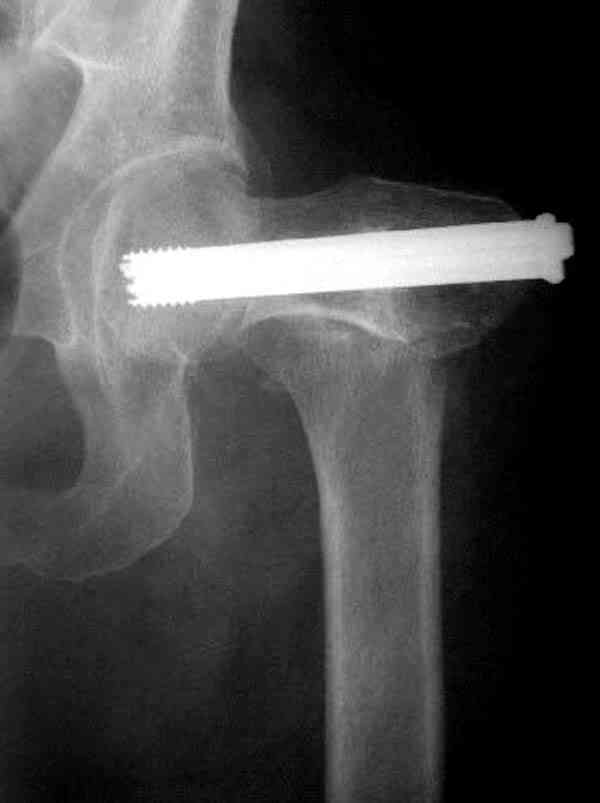

На Московской конференции в ноябре была продемонстрирована удивительная методика профилактического армирования шейки бедра у пациенток с остеопорозом и переломом контрлатеральной шейки в анамнезе.Странно, но дискуссии это сообщение не вызвало.Кто что думает об этом?

Спасибо, Антон. Я автор того сообщения по профилактическому армированию шейки бедренной кости, которое прозвучало на конференции, посвященной 50-летию создания АО. Мне тоже хотелось услышать вопросы по теме. Мы травматологи-ортопеды в первую очередь хирурги, а не терапевты. Почему в вопросе профилактики и лечения остеопороза мы ограничиваемся только консервативными методами лечения? Как можно практически научить больного не получать травмы, когда немало случаев возникновения переломов даже в постели. Первоначально идея армирования ШБК многих, при ком я озвучивал ее, шокировала, затем возникала дискуссия и большинство поддерживали эту идею. Мне бы очень хотелось развернуть дискуссию на странице этого сайта.

Уважаемый Антон! У меня было всего три клинических наблюдения, снимки были продемонстрированы на московской конференции. Количества этих снимков хватило для подачи заявки, а затем и получения патента на изобретение. В свое время РОСПАТЕНТ потребовал подтверждения методики клиническими наблюдениями. У одной из больных действительно произошла повторная травма, и произошел подвертельный перелом на стороне армированной шейки бедренной кости (см. снимки). Это подтвердило основную идею изобретения - была сохранена и головка, и армированная шейка бедренной кости. Но тут не обошлось безпроблем. Анестезиологи отказались давать наркоз, а провести остеосинтез под м/а пластиной и винтом DHS не согласилась больная. Дальнейшее лечение скелетным вытяжением. На контр. Рентгенограмме через 2 месяца признаки формирования костной мозоли. Повторных обращений двух других пациентов не было. Для более детальных исследований и выводов необходимо значительно большее количество клинических наблюдений. Такие исследования могли быть проведены в условиях клиник медуниверситета. Напомню, я работаю в травмотделении провинциальной городской больницы. Насчет экспертов страховых компаний, так пусть они выскажут свое мнение. Армирование кости - это плановые операции по желанию больного, какие здесь могут быть противоречия? На армирование все больные, к моему удивлению, согласились довольно легко и сразу, поэтому остеосинтез и армирование были проведены в течение одной операции. С уважением А.М.

В идеале для профилактики рефрактуры шурупы надо вводить не больше, чем под 130 градусным углом и не ниже уровня малого вертела.

Насчет биомеханических преимуществ одного шурупа тоже возникает вопрос. Если придерживаться канонов механики, для перелома шейки необходимо 3 паралельных шурупа, расположенных ближе к кортикальному слою шейки.